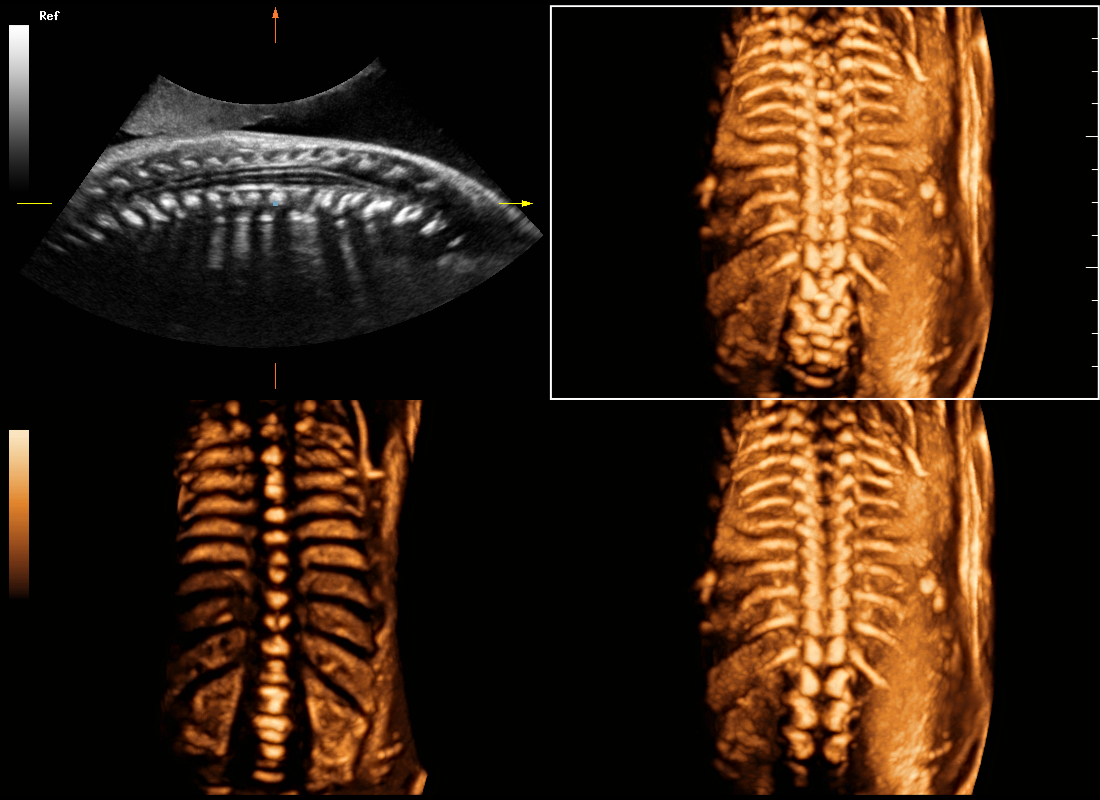

Central nervous system (CNS) malformations are one of the most common congenital abnormalities. Unfortunately, due to imaging limitations such as poor fetal position, acoustic shadowing, and operatorsŌĆÖ poor scanning skills, the MSP is particularly difficult to find in a 2D ultrasound. In this case, a faster and more user-friendly method, which automatically displays the standard planes together with the required measurements in a fetal CNS examination, could significantly boost both the quality and efficiency of clinical diagnoses.?NuewaŌĆÖs intelligent solution of fetal brain can realize automatic acquisition of brain volume data based on intelligent recognition of CNS application scenarios, intelligent generation of four fetal brain standard planes including MSP, automatic measurement of CNS biological items and automatic evaluation of fetal brain volume. More importantly, Nuewa's leading color Doppler technology can provide a clear and sensitive dynamic display of blood flow in the tiny vessels.